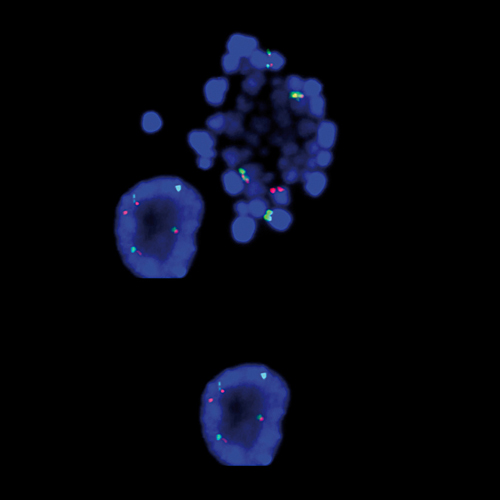

KMT2A / MLLT4 t(6;11) Fusion probe hybridized to patient material showing 47,XX,t(6;11)(q27;q23),+der(6)t(6;11) (q27;q23).

One of the relatively frequently observed translocations in AML involves the genes KMT2A and MLLT4 (previously known as AF6) at 11q23 and 6q27. The KMT2A/MLLT4 translocation results in the generation of fusion protein that retains the KMT2A N-terminus, including both an A-T hook domain and a region similar to mammalian DNA methyltransferase. The breakpoint region of the MLLT4 gene is located within intron 1 and downstream of the initiation codon. The KMT2A/MLLT4 t(6;11) Fusion FISH probe is optimized to detect translocations involving the KMT2A (previously known as MLL) and MLLT4 gene regions at 11q23 and 6q27 in a dual-color, fusion assay on metaphase/interphase spreads, blood smears and bone marrow cells.